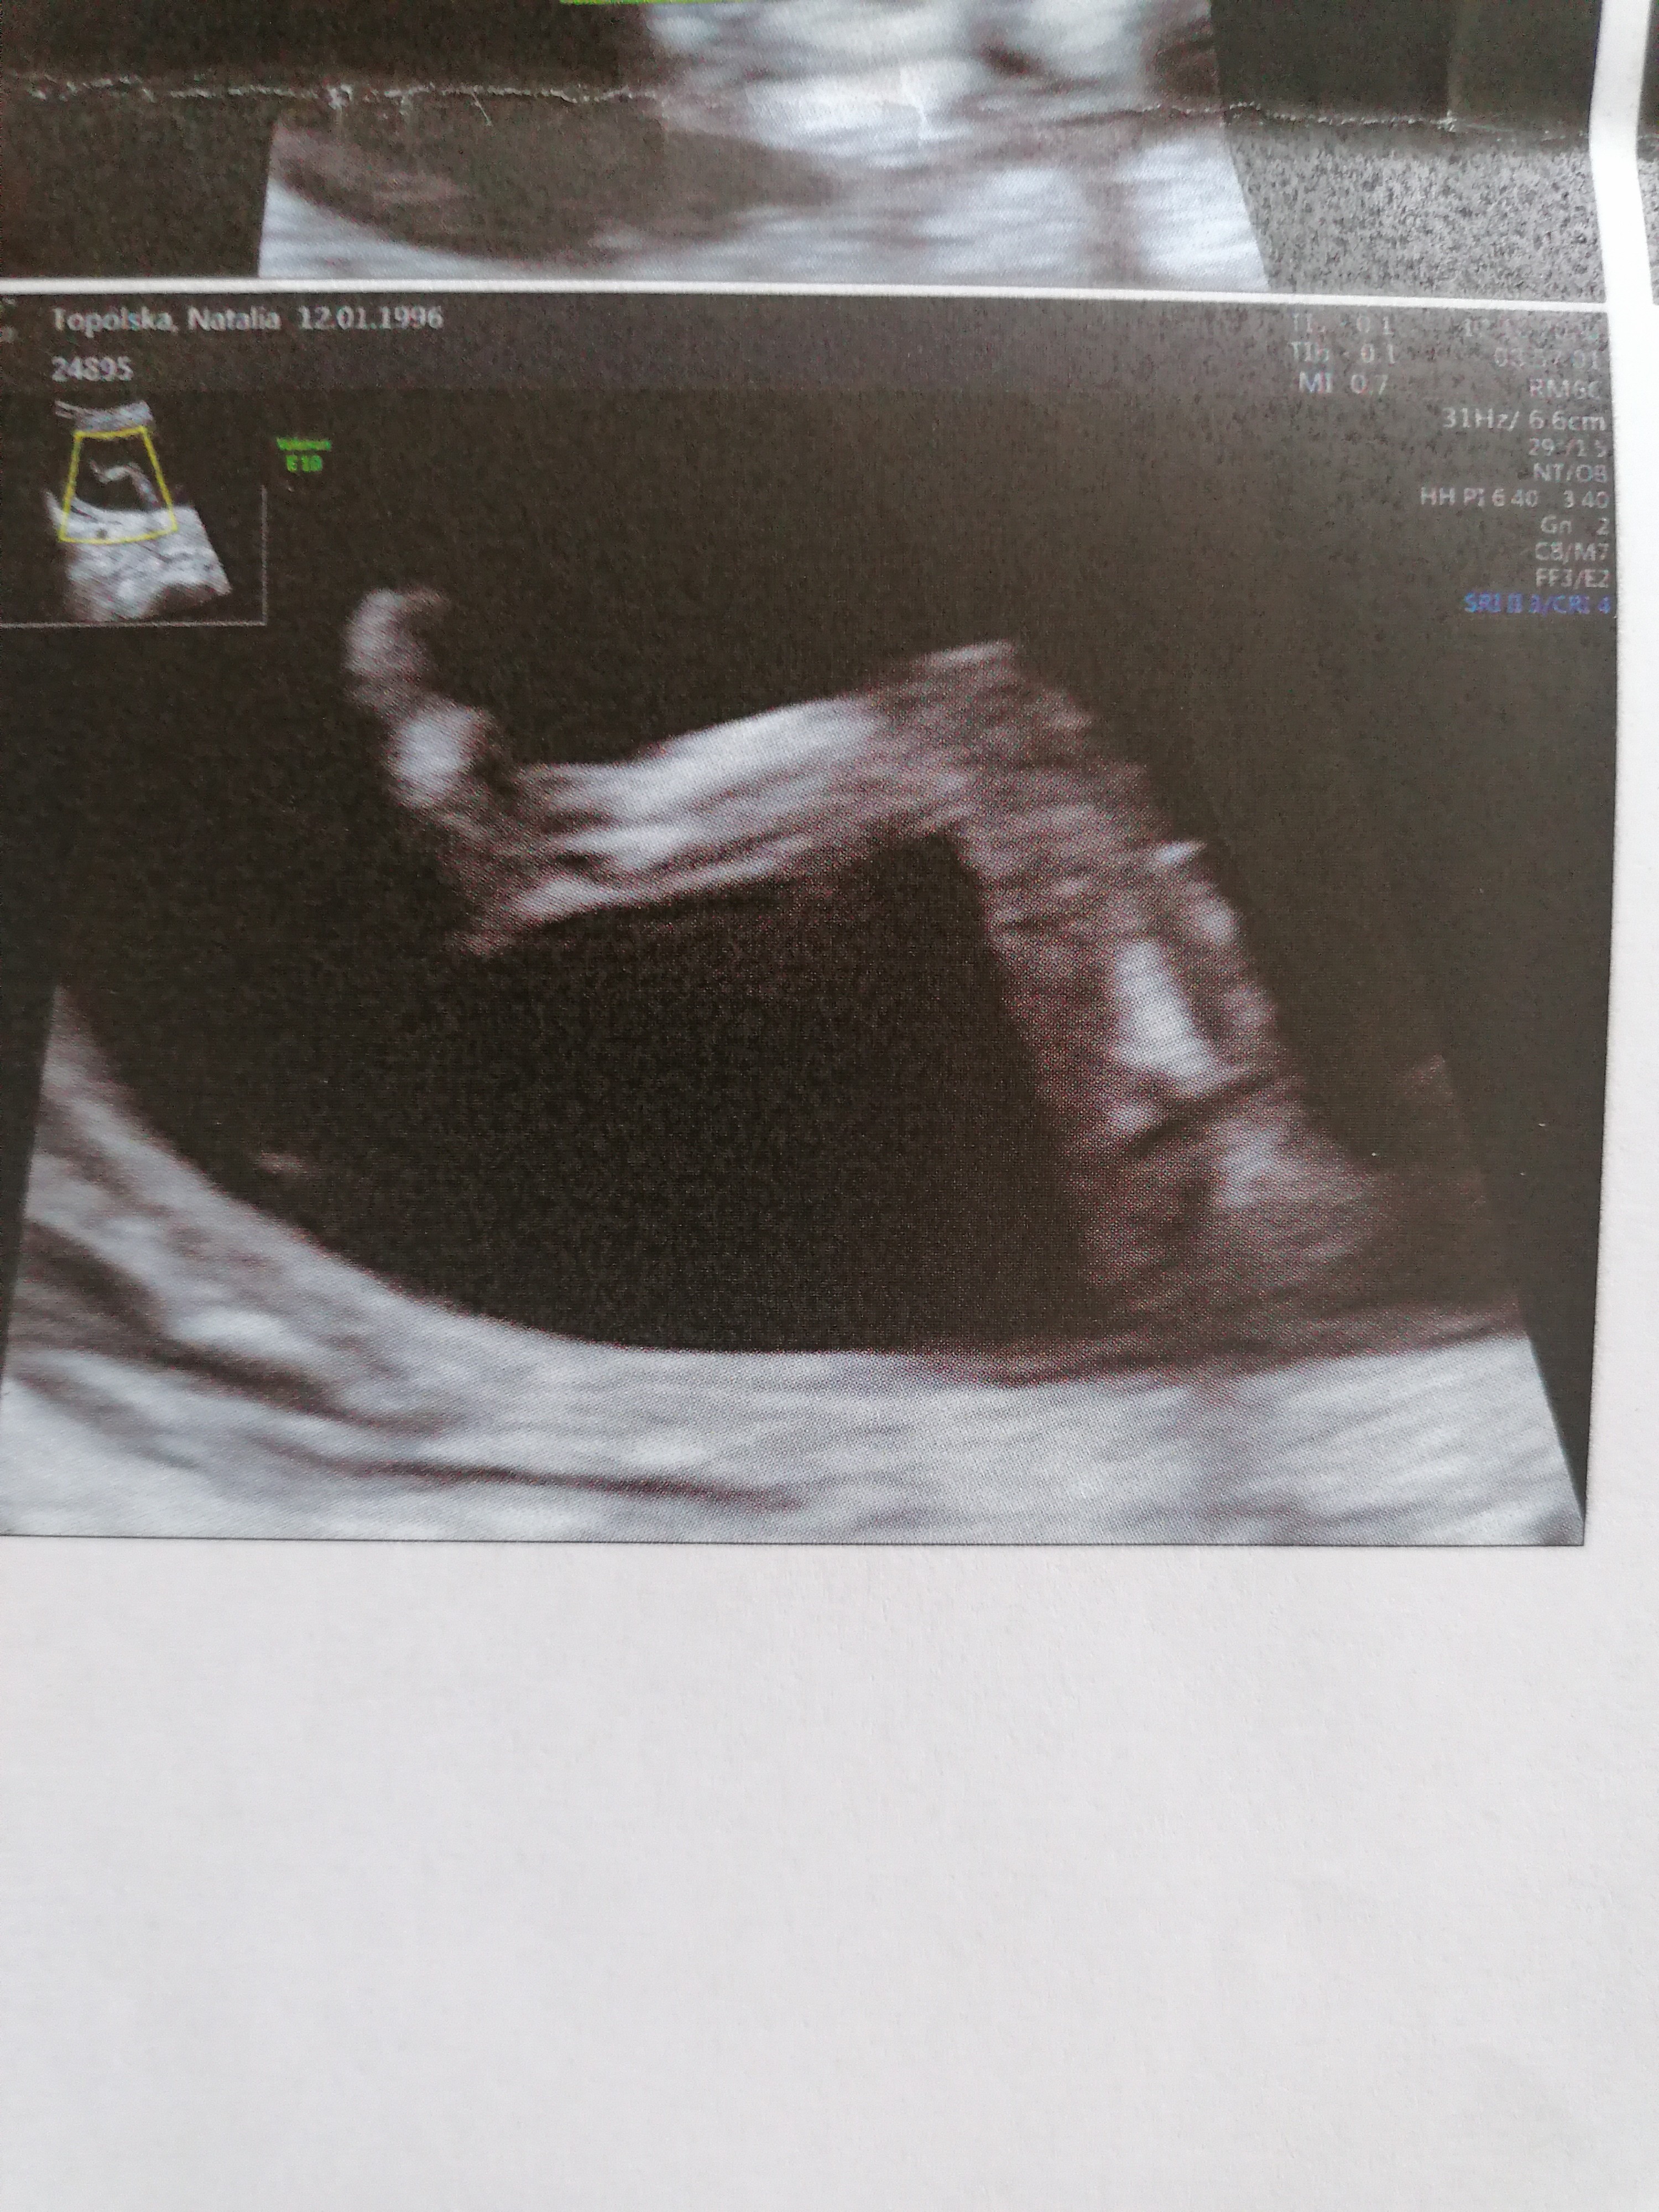

Jestem już po badaniach prenatalnych. Płci za bardzo widać nie było, nie chciała wróżyć ;) Najważniejsze, że z dzieciątkiem wszystko w porządku! 🥰 Wszystkie parametry idealne, teraz czekać na wynik z krwi. Ta noga mnie rozczuliła ❤ IMG_20201012_125617.jpgIMG_20201012_125443.jpg